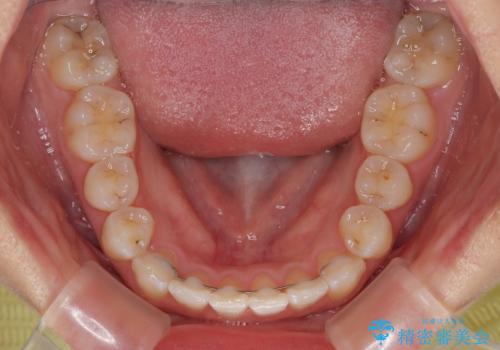

前歯のクロスバイト 裏側に隠れた歯をワイヤー装置で短期間治療

- 矯正装置

- メタルブラケット

- 上顎前歯のクロスバイトを気にして来院された患者様です。

ワイヤー矯正でもマウスピース矯正でも対応可能でしたが、マウスピースによる自己管理に一切の自信がないとのことで、ワイヤー装置にて矯正治療を行うこととしました。

装置の外見を気にしていましたが、短期間で治療を終えることができるだろうと伝えると、安価であるメタルブラケットを選択されました。

想定通り、1年強で綺麗に仕上げることができました。